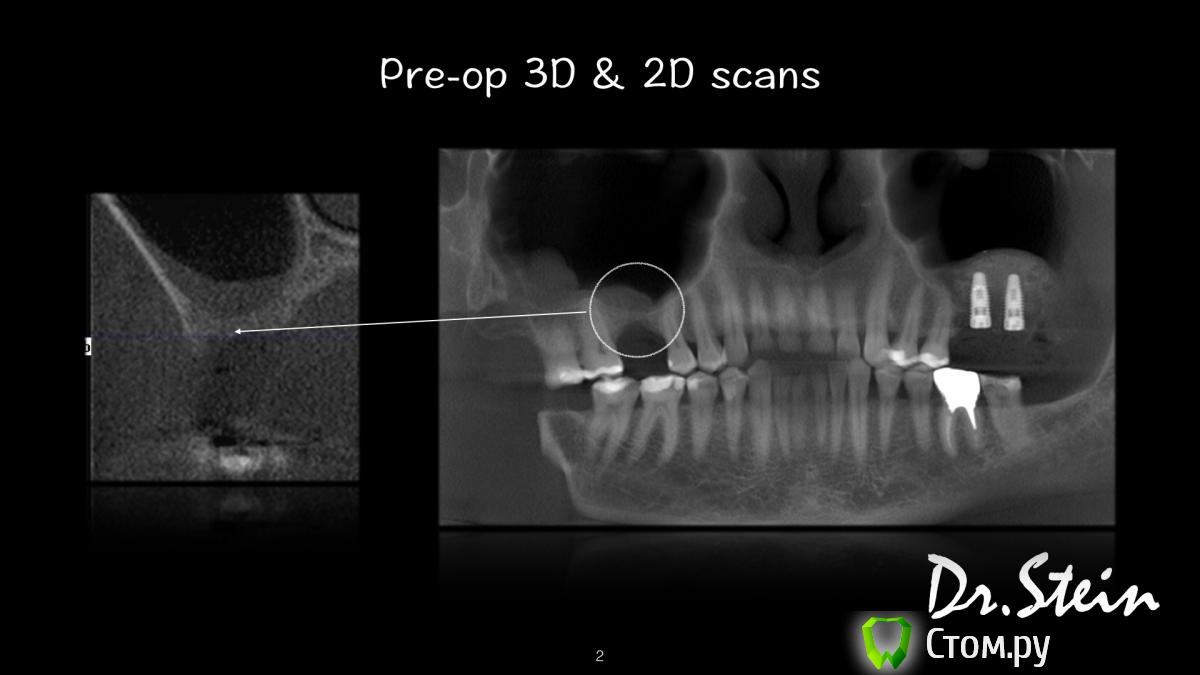

Dr.Stein Опубликовано 27 января, 2014 Автор Поделиться Опубликовано 27 января, 2014 (изменено) А просто синусом там вообще никак не обойтись было? Спасибо, что выкладываете!Надеюсь критика только раззодорит)) Ладно бы такая травматичность, ещё как- то улучшила бы прогноз.. Ан нет.. Вощем можно было всё разом, без блоков, а при хорошем торке даже фдм..выкладывал похожий случай с худшим гребнем.. Если надо, могу ещё)) Объясню свою логику.Двумя неделями ранее я ставил этому пациенту 2 импланта слева, одномоментно с синусом. В области 2.7 было примерно столько же кости, плотность D4, торк 2-3 H.В этом сегменте плотность кости аналогичная, ФДМ сразу я бы точно ставить не стал.Для того, чтобы обойтись одним только синусом пришлось бы снять около 3 мм кости вестибулярно и соответственно поднять на 3 мм ортопедическую платформу. Соотношение высоты тела импланта и супраструктуры на этапе протезирования изменилось бы в пользу последней. А это по моему мнению неуместно в подобной ситуации. А насиловать синус, поднятый с двух миллиметров болтами 13 и больше я точно не стану, да и это мало что изменит, мы же прекрасно знаем, что плотность аугментата после синуслифтинга очень часто оставляет желать лучшего. Поэтому предпочел не рисковать, и попытался воссоздать анатомическую форму гребня. Для того, чтобы имплант стоял хотя бы в 4 - 5 мм кости нормального качества, что здорово снизит шансы его "утопления" в синус через полгода после нагрузки Carloss, конечно надо, выкладывайте! Изменено 27 января, 2014 пользователем Dr.Stein Ссылка на комментарий